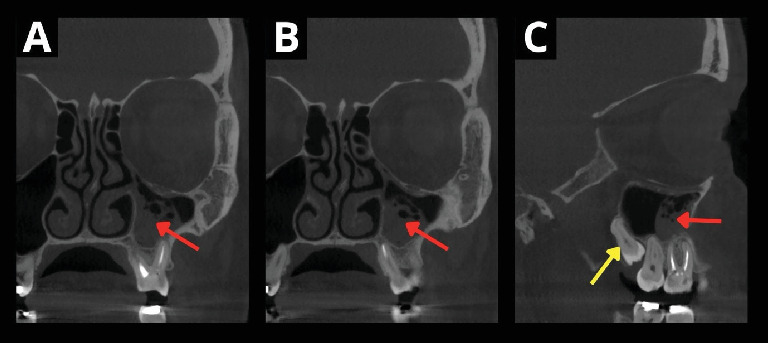

自体牙移植的效果主要取决于移植牙的解剖结构、供牙的类型和牙根形成的发育阶段。成熟牙由于牙髓血运重建潜力较低,并发症发生率较高,需要术前或术后进行根管治疗(RCT)以避免术后并发症,延长了治疗时间和费用。本文报告了一位39岁的患者在根管再治疗失败后,自体移植一颗成熟的智齿来代替第一磨牙。在手术中,移植的牙齿在放置之前进行了口外根切除,以避免需要提升施耐德膜,在手术切除上颌窦囊性病变后,施耐德膜显示不完全愈合。术前和术后均未进行随机对照试验。在3年的随访中,牙齿无症状。使用标准的活力测试难以确定自体移植牙的活力,这取决于患者的主观反应,但使用脉搏血氧仪客观地证实了这一点。本病例不仅显示了老年患者成熟牙移植血运重建的可能性,也为如何客观地确认和测量自移植牙的血运重建提供了可能的术后方案。

The outcome of tooth autotransplantation depends mainly on the transplant tooth's anatomy-the type of donor tooth and the developmental stage of root formation. Mature teeth display a higher complication rate due to lower pulp revascularization potential, requiring root canal treatment (RCT) pre- or postoperatively to avoid postoperative complications, which extends treatment duration and cost. This report details a 39-year-old patient's autotransplantation of a mature wisdom tooth to replace the first molar after unsuccessful root canal retreatment. During the surgery, an extraoral root resection of the transplanted tooth was performed prior to placement to avoid the need to elevate the Schneiderian membrane, which displayed imperfect healing following the surgical removal of a cystic lesion in the maxillary sinus. RCT was not performed before nor after the procedure. At the 3-year follow-up, the tooth was asymptomatic. The vitality of the autotransplanted tooth was difficult to determine using standard vitality tests, which depend on patients' subjective responses, but the use of pulse oximetry objectively confirmed this. This case not only shows the possibility of a mature tooth transplant revascularization in an older patient but also gives a possible postoperative protocol of how to objectively confirm and measure the revascularization of the autotransplanted tooth.